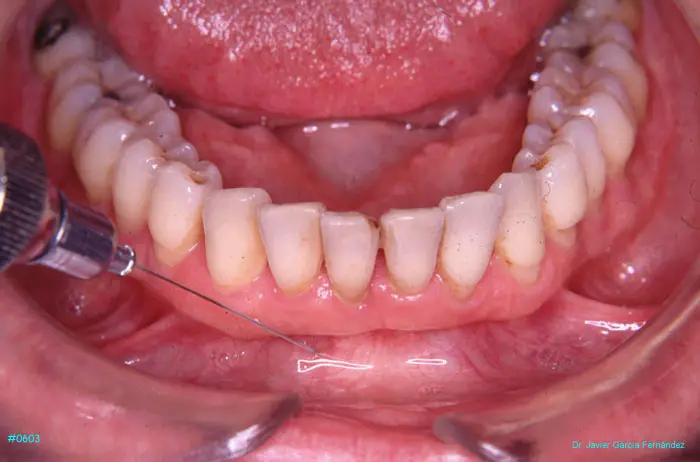

Atlas of Surgical Techniques in Periodontics. Chapter II. Atlas de Técnicas Quirúrgicas en Periodoncia